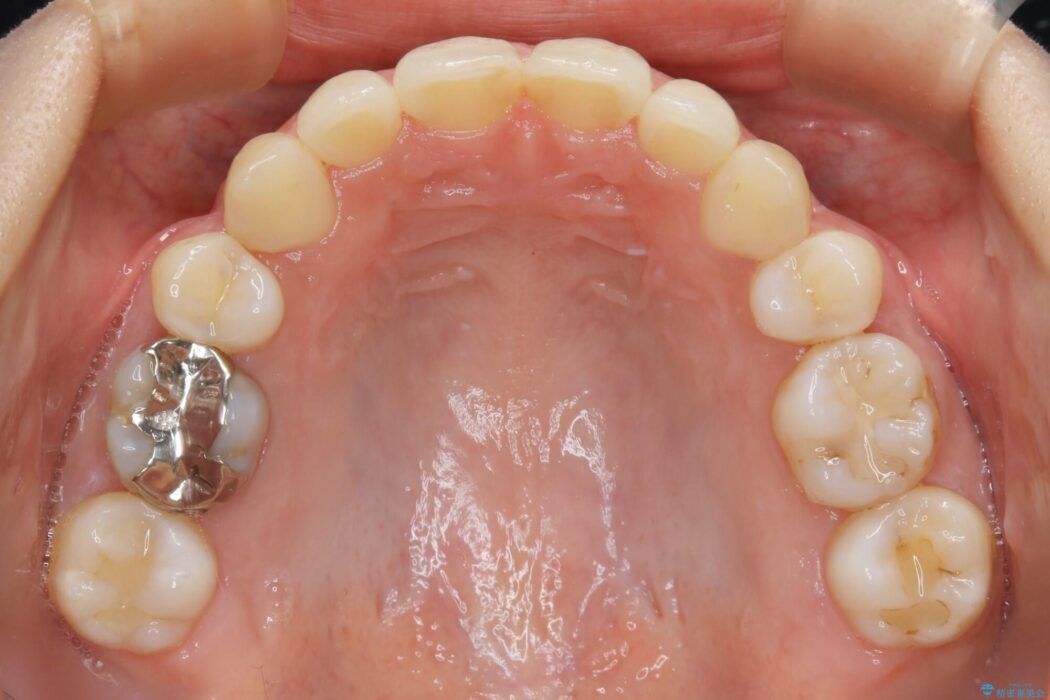

【20代女性】抜歯矯正で叢生をなおす

ガタガタな歯並びをなおしたいとのことで来院されました。

左右の奥歯が前方に寄っていることにより八重歯の発生や重度の叢生に繋がっていました。

ですが詳しく検査をしたところ、左右の奥歯の前後位置に関してはズレが少ない状態でした。

加えて患者様の顎の大きさに対する歯の数が多いことが叢生の原因になっていることから、抜歯した上で歯列を整えるほうが最終的な仕上がりとして良い結果になると判断しました。

まず噛み合わせに問題が少ない奥歯の位置を極力変えないように上下左右4番目の歯を抜歯することで歯列矯正のためのスペースを確保し、空いた隙間で前歯の凹凸をきれいに並べていくこととしました。

笑った時に見えるガタついていた見栄えが改善されて歯列弓もきれいな形に整い、患者様にはご満足いただけました。